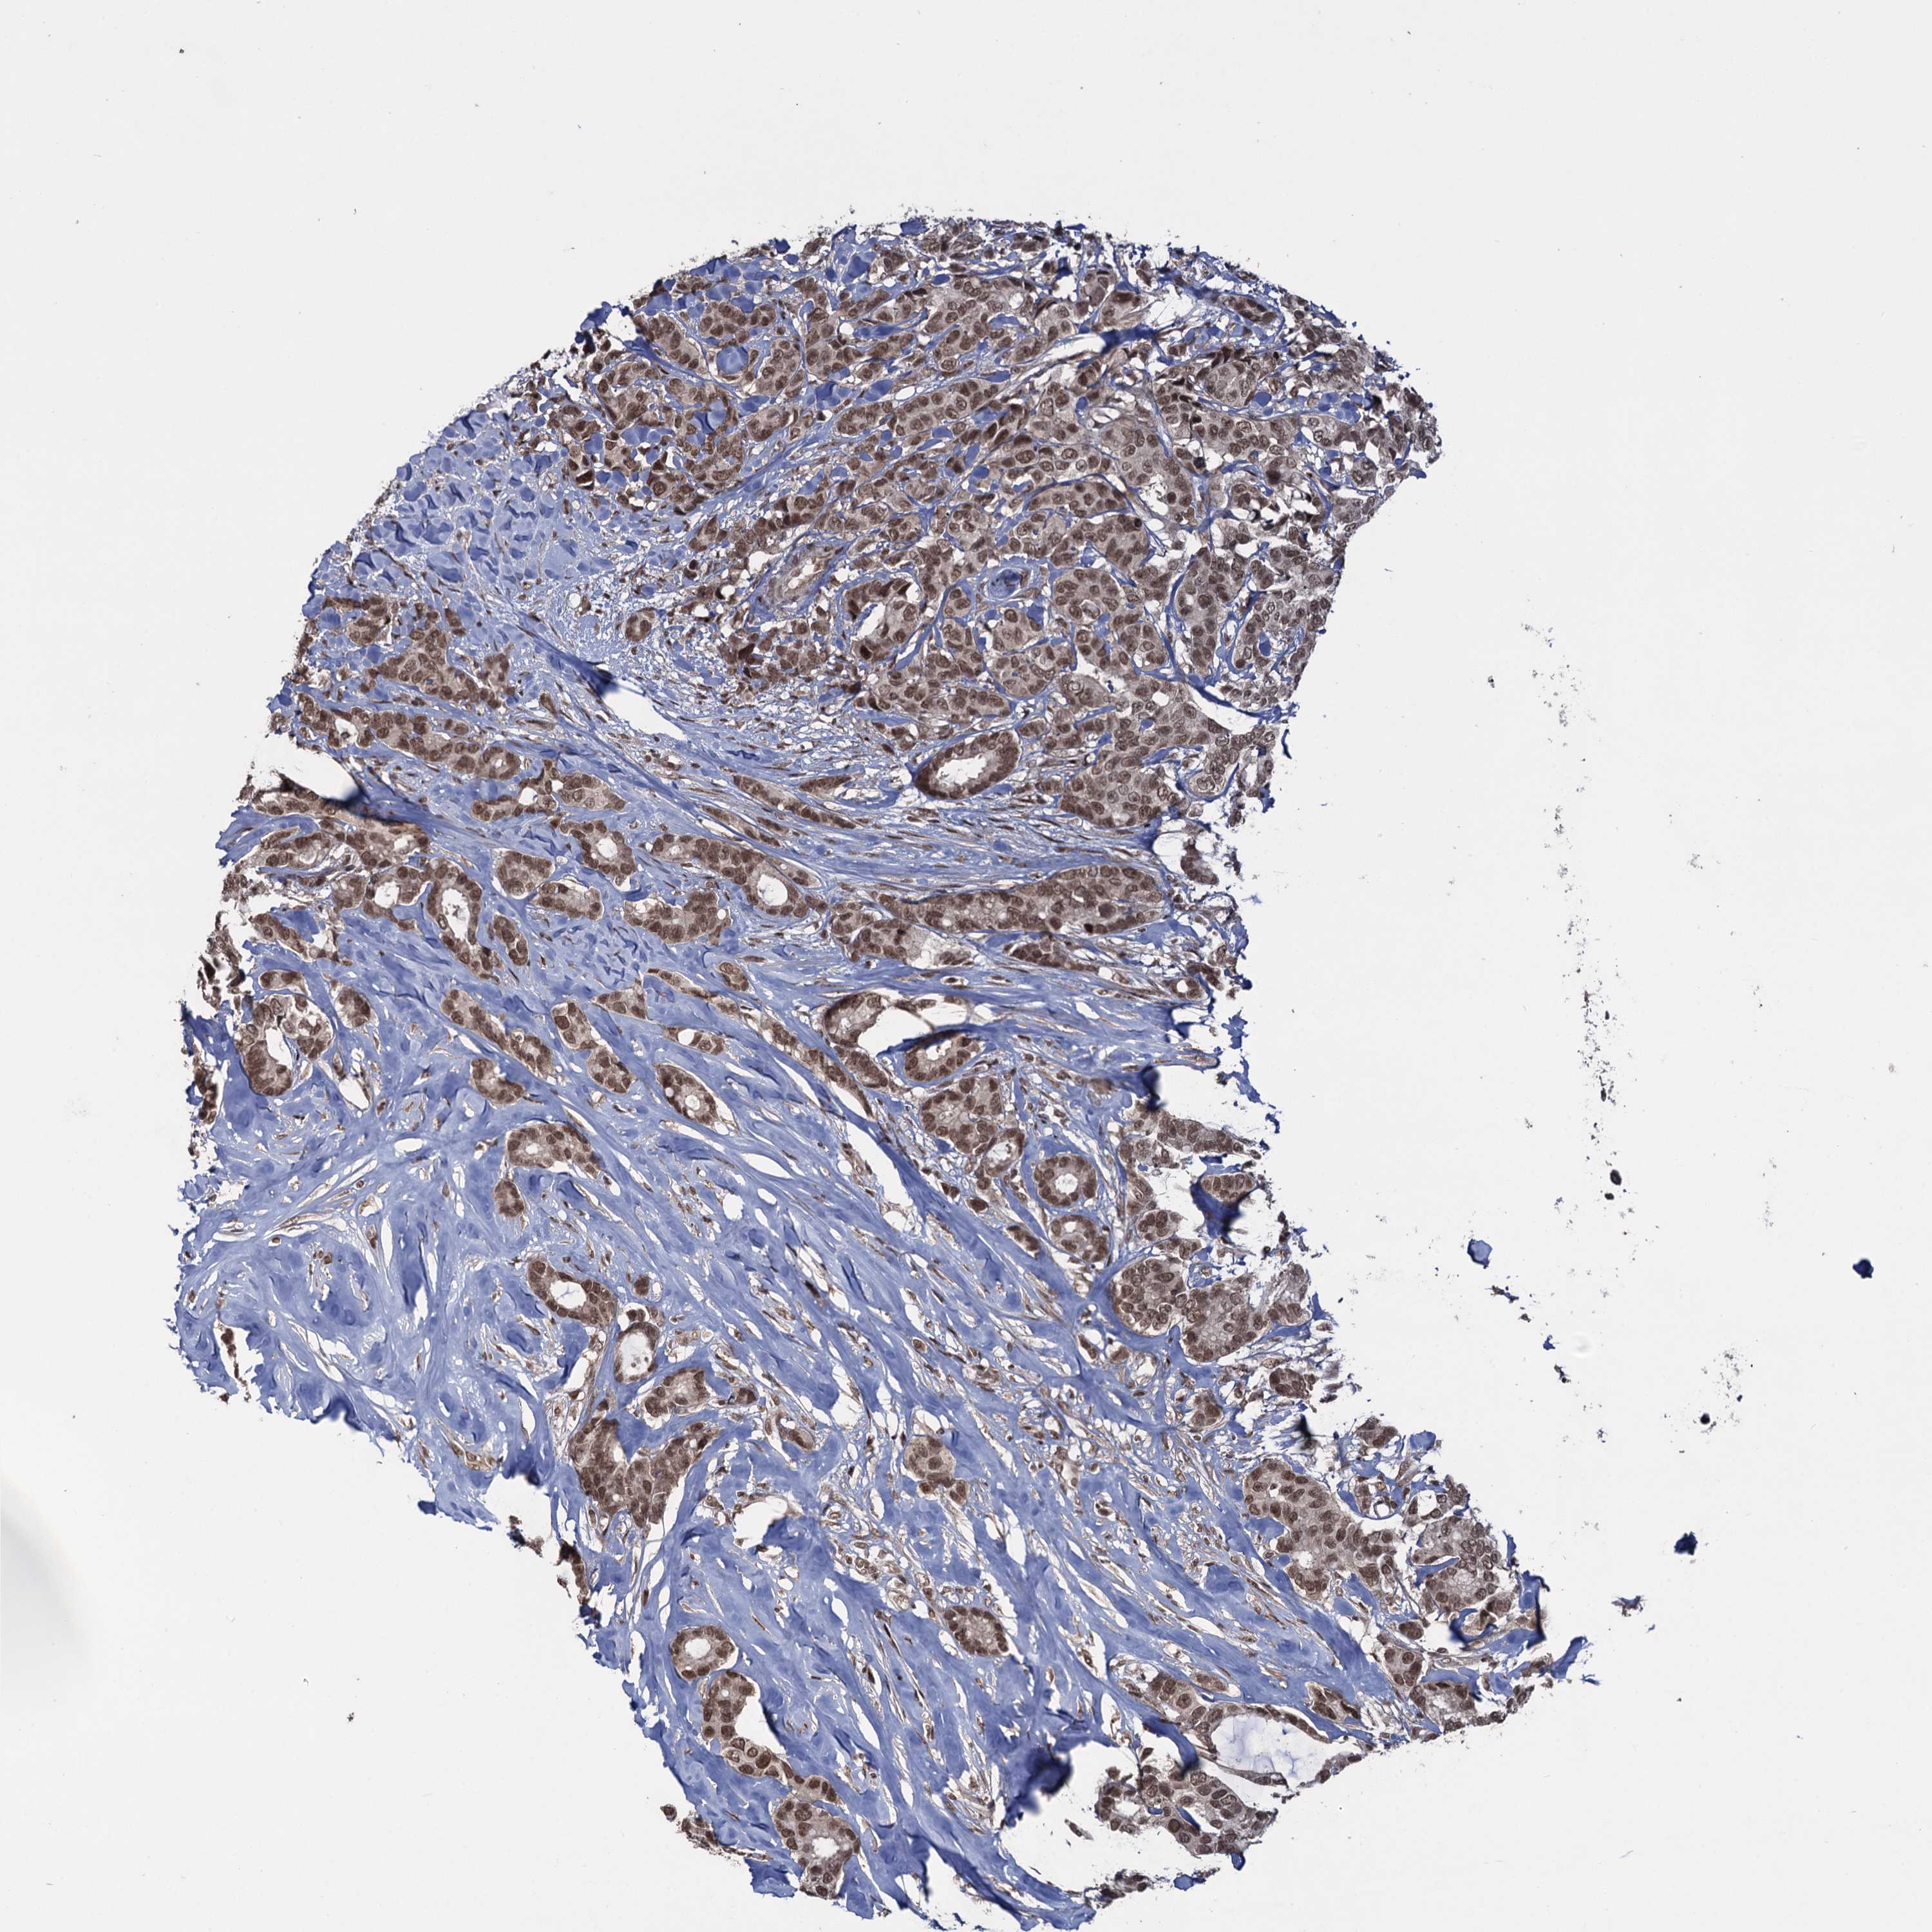

CANCER BREAST CANCER Show tissue menu

BRCA TCGA BRCA VALIDATION PROTEIN EXPRESSION

Breast cancer

Human cancer

Breast invasive carcinoma